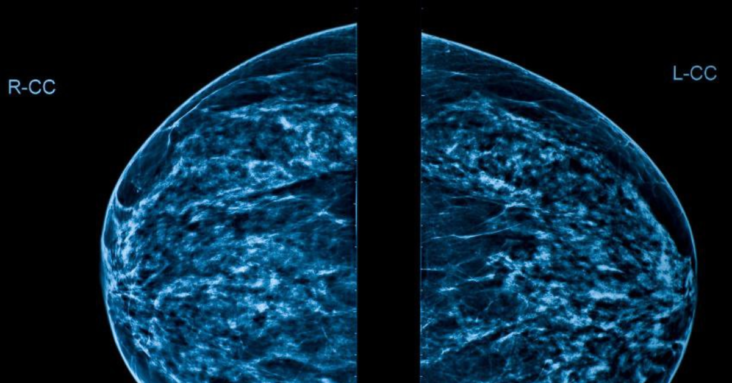

The mammogram was up on the computer screen — with five bright spots! The tech explained that the spots were lymph nodes that inflame post-Covid vaccine! She said at first Radiologists were referring back to the PCP to rule out infection. Then they started biopsies. Finally, they determined that the inflamed lymph nodes were a result of the Covid vaccine! I asked her how long this will last. Her somber answer was, “We just don’t know.”